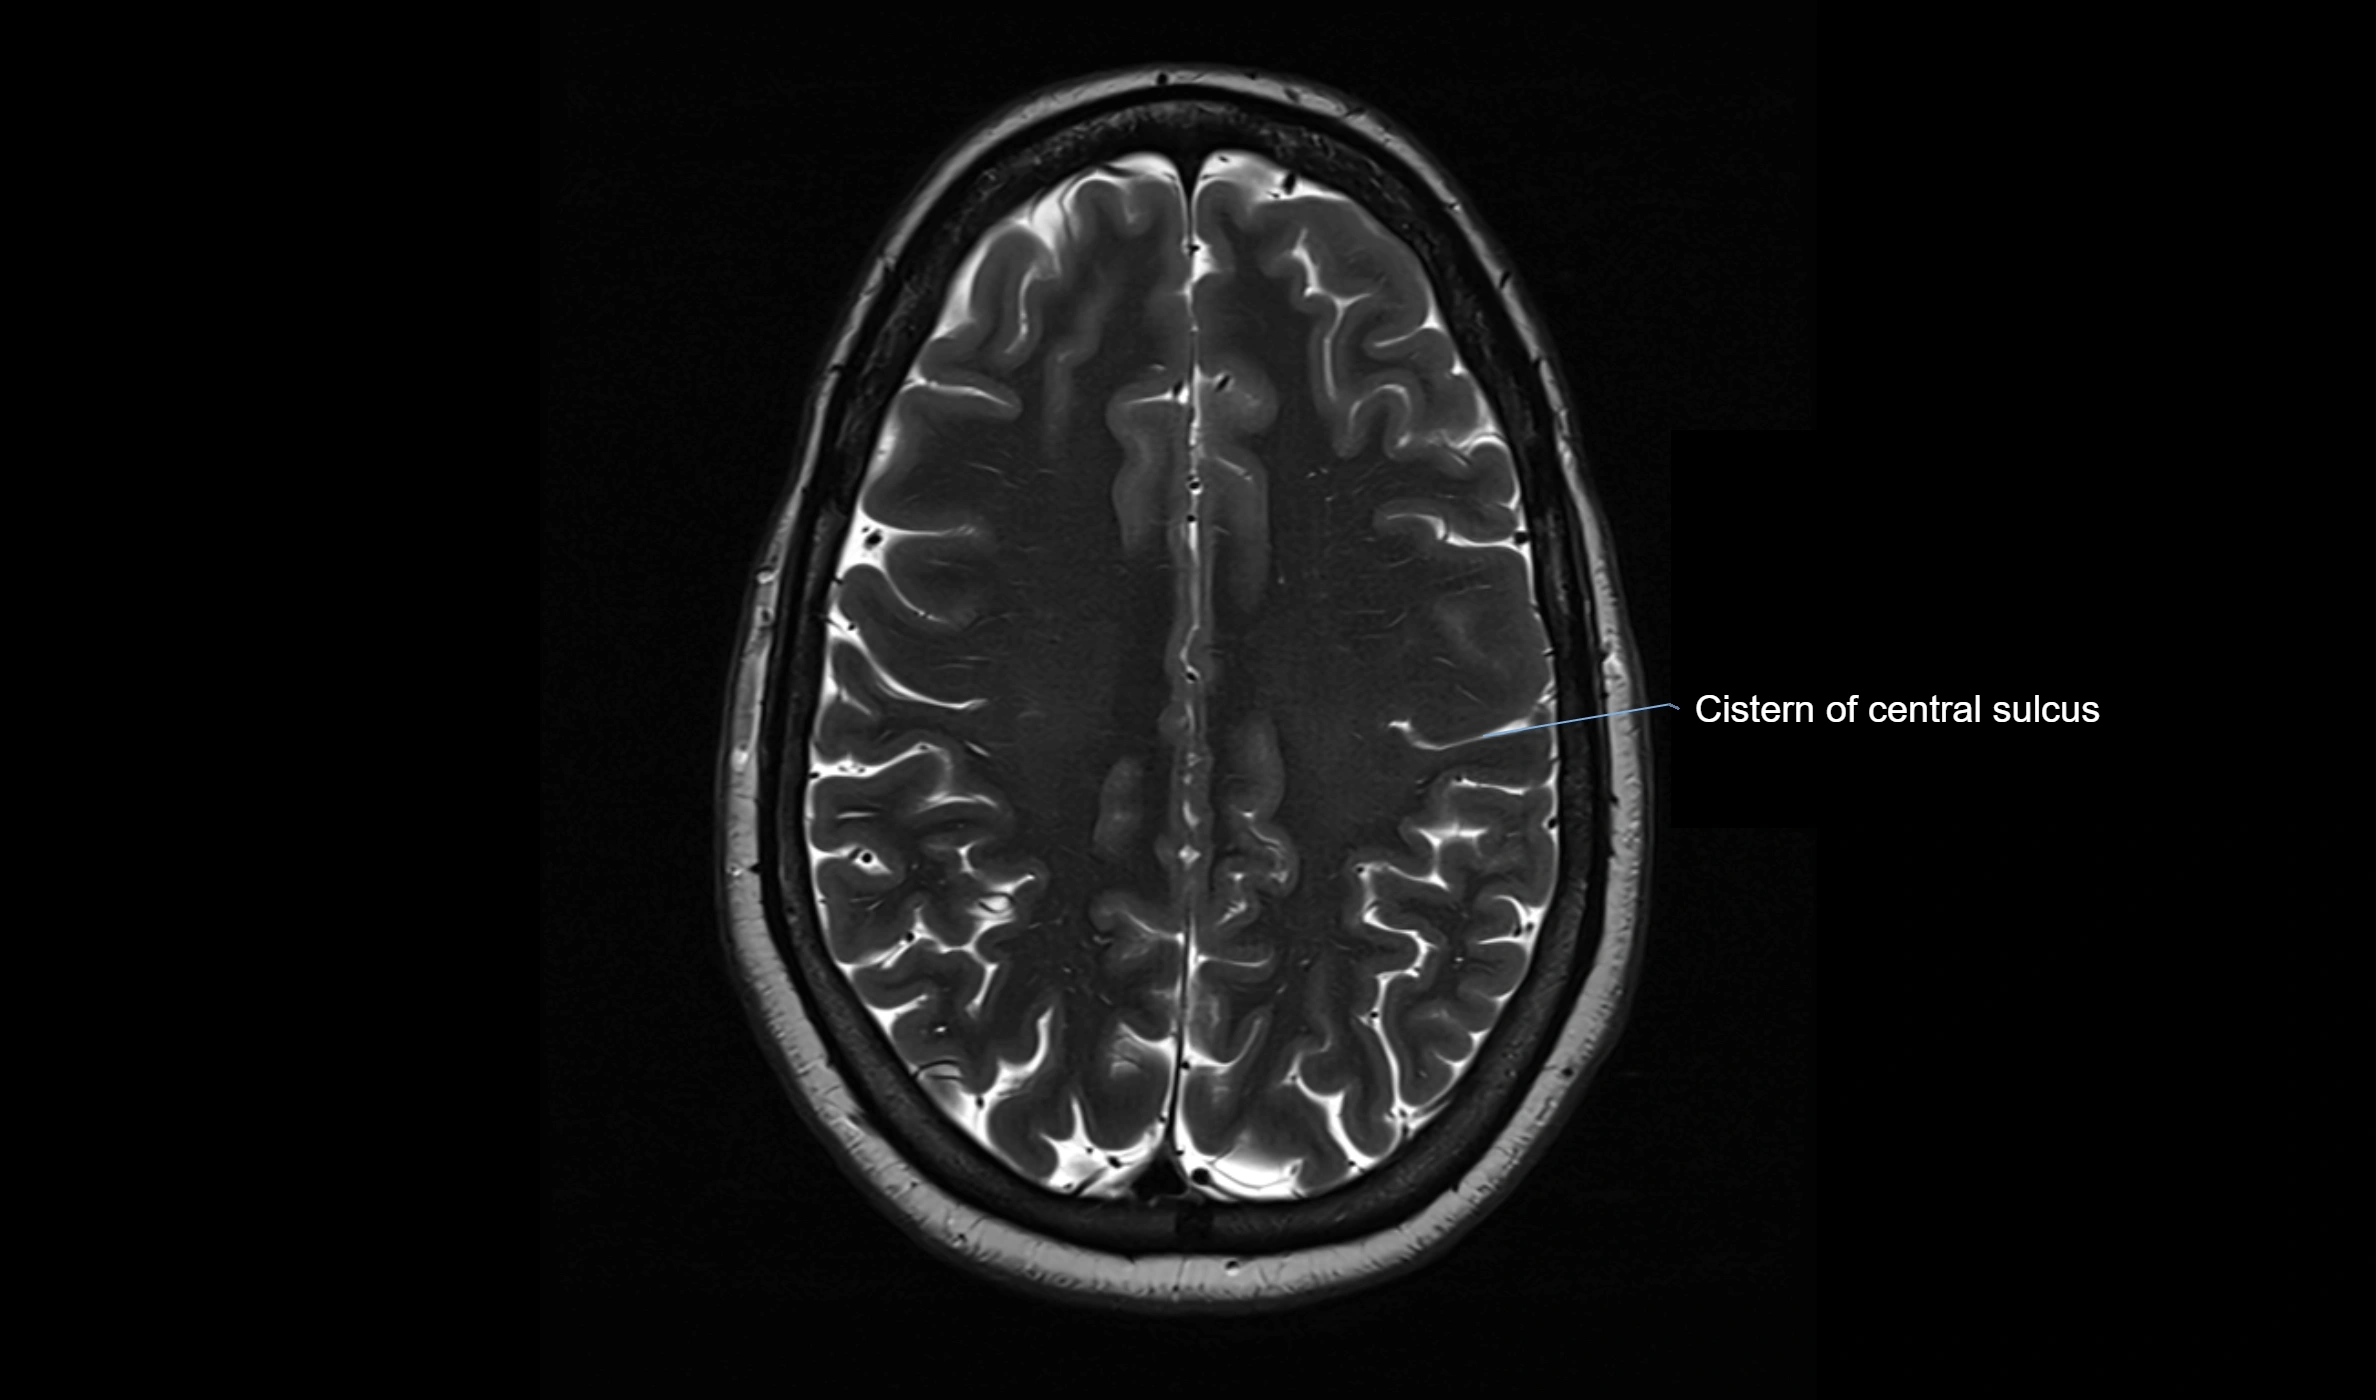

MRI images

image